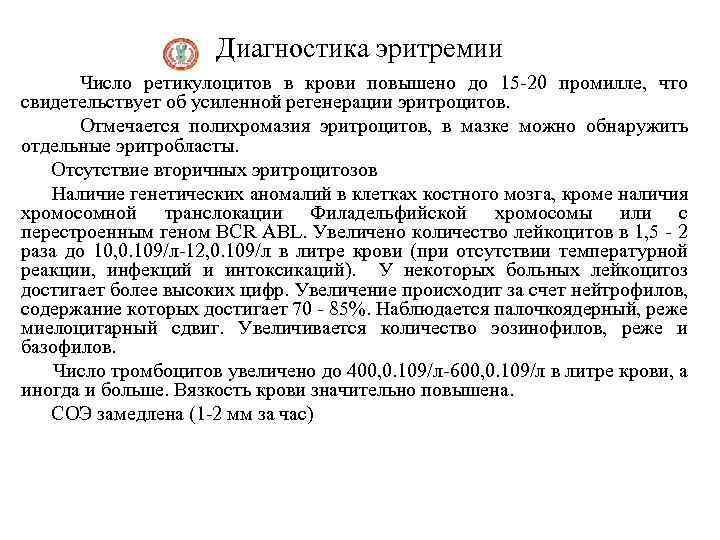

Диагностика эритремии Число ретикулоцитов в крови повышено до 15 -20 промилле, что свидетельствует об усиленной регенерации эритроцитов. Отмечается полихромазия эритроцитов, в мазке можно обнаружить отдельные эритробласты. Отсутствие вторичных эритроцитозов Наличие генетических аномалий в клетках костного мозга, кроме наличия хромосомной транслокации Филадельфийской хромосомы или с перестроенным геном BCR ABL. Увеличено количество лейкоцитов в 1, 5 - 2 раза до 10, 0. 109/л-12, 0. 109/л в литре крови (при отсутствии температурной реакции, инфекций и интоксикаций). У некоторых больных лейкоцитоз достигает более высоких цифр. Увеличение происходит за счет нейтрофилов, содержание которых достигает 70 - 85%. Наблюдается палочкоядерный, реже миелоцитарный сдвиг. Увеличивается количество эозинофилов, реже и базофилов. Число тромбоцитов увеличено до 400, 0. 109/л-600, 0. 109/л в литре крови, а иногда и больше. Вязкость крови значительно повышена. СОЭ замедлена (1 -2 мм за час)